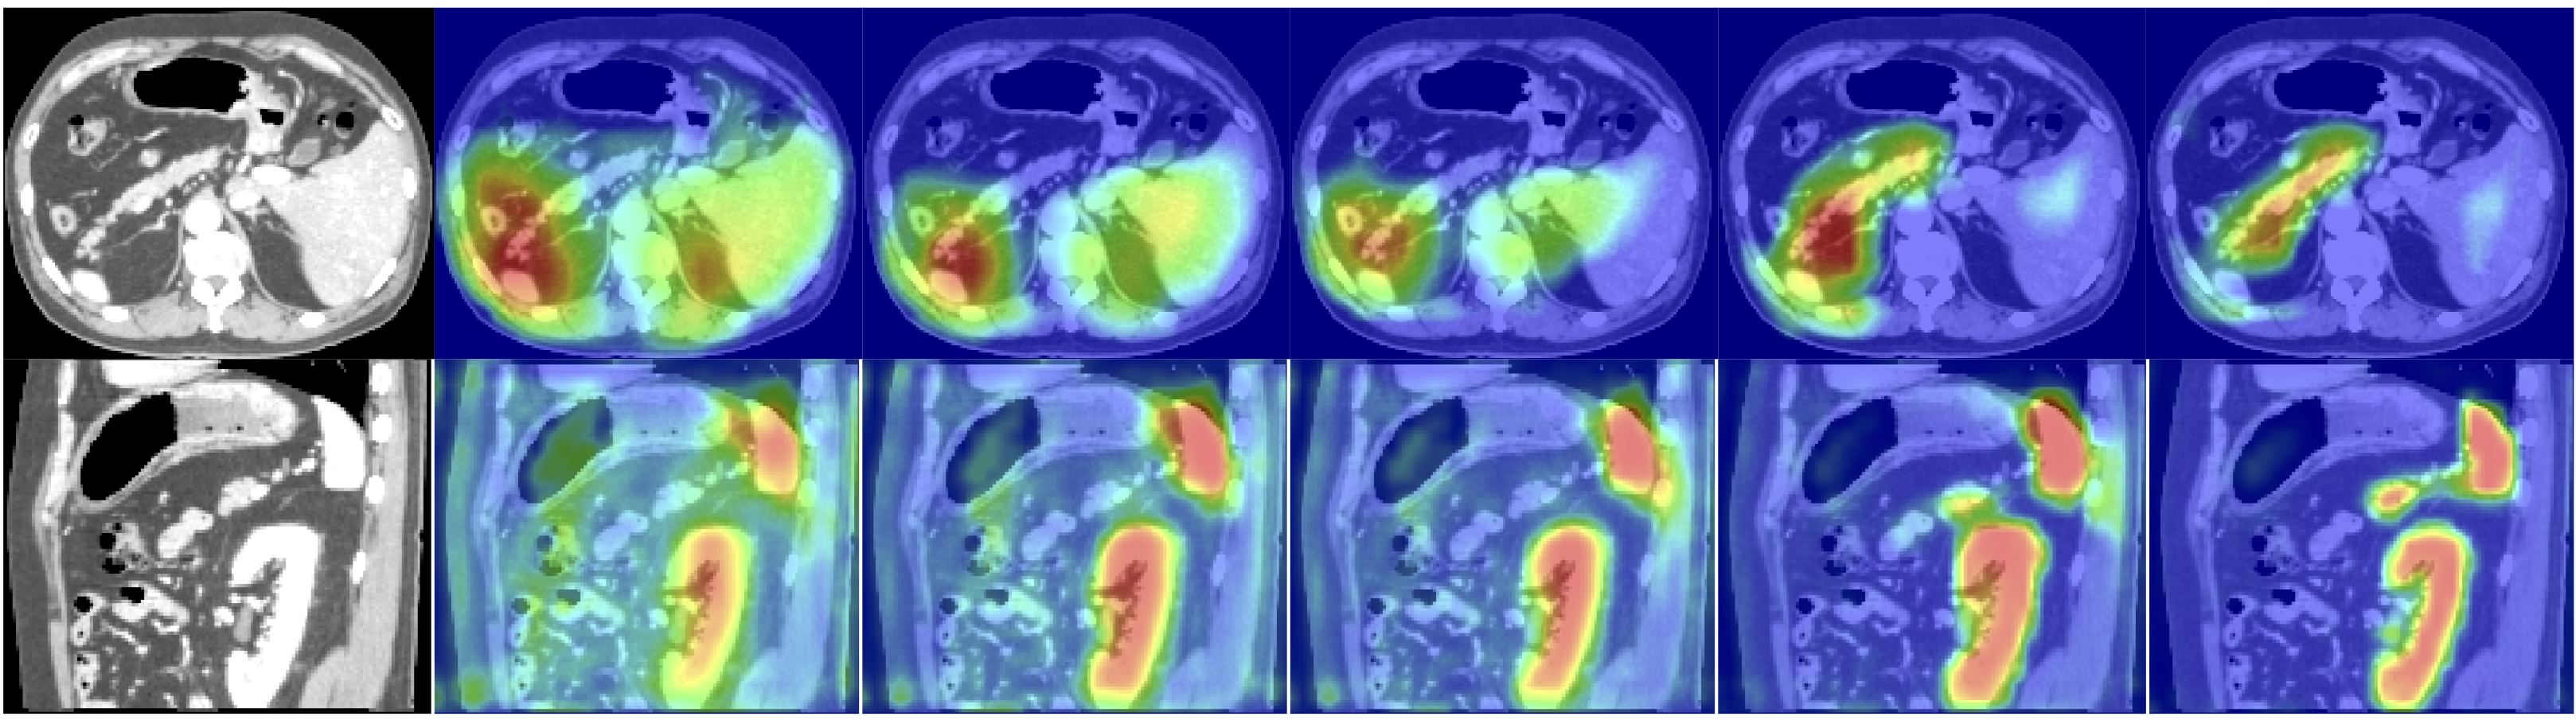

Attention Map Analysis: The attention coefficients obtained from test images are visualised with respect to training epochs (see Figure 4). We commonly observe that AGs initially have a uniform distribution and pass features at all locations. This is gradually updated and localised towards the targeted organ boundaries. Additionally, at coarser scales AGs provide a rough outline of organs which are gradually refined at finer resolutions. Moreover, by training multiple AGs at each image scale, we observe that each AG learns to focus on a particular subset of organs.